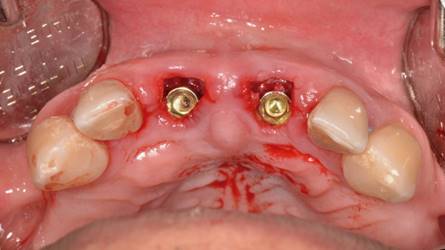

Posteriormente se realizó una impresión de alginato y vaciado en yeso del maxilar, se eliminaron mecánicamente ambos incisivos centrales. Este modelo se digitalizó con un escáner extraoral (3Shape, Trios) y se obtuvo un archivo STL. Luego con esto datos se hizo una coincidencia digital entre el CBCT y el archivo STL, utilizando el software BlueSky plan, (BlueSky bio). Se planificaron dos implantes cónicos de conexión interna de 3.8 x12 mm (Biohorizons), separados de la parte vestibular de las raíces y asegurando su correcto posicionamiento implantario (Img 1). Luego se diseñó una guía quirúrgica en el mismo software, exportada e impresa en ácido poliláctico (PLA) por una impresora de tecnología de deposición de material fundido (FDM) (Duplicator 7, Wanhao, China). Después de la anestesia local, se extrajo la porción coronal de ambos dientes fracturados, luego las partes apicales restantes se dividieron mesio-distalmente con una fresa de diamante de alta velocidad dejando dos porciones. Se retiró la parte palatina y se conservaron 5 mm de la pared vestibular radicular, posteriormente se instaló la guía quirúrgica en posición (Fig 2 y 3).

El protocolo de fresado llegó a los 21 mm de profundidad y a la fresa de 3.2 mm de diámetro. Ambos implantes alcanzaron 40 N de torque, todo bajo un protocolo de cirugía e inserción guiada estricta de implantes (Fig. 4).